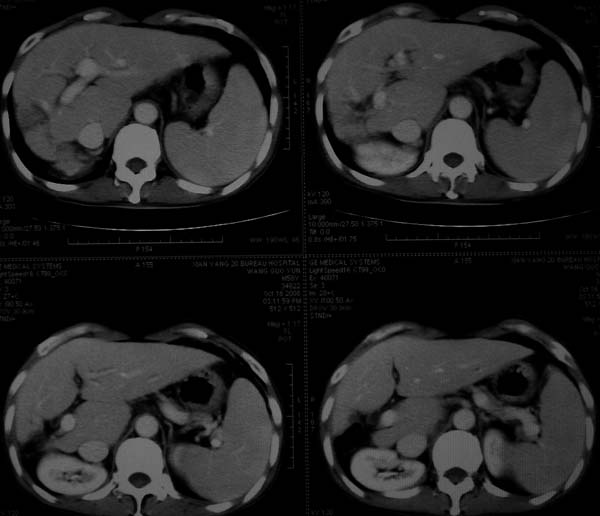

标题: CT16292:男,53岁,上腹部不适2月,B超发现肝内占位病变。 [打印本页]

标题: CT16292:男,53岁,上腹部不适2月,B超发现肝内占位病变。

符合肝ca增强,\"快进快出\";肝叶比例失常,右叶萎缩,肝裂增宽,脾大,肝硬化可能.

肝脏体积变小,肝裂增宽,分布异常,肝尾叶增大,脾肿大,考虑肝硬化可能性大,右肝病灶呈现早期充盈,延迟强化考虑肝内胆管细胞癌可能,不除外血管瘤

肝硬化,多结节肝癌。比较典型的表现了。

肝叶比例失调,左叶增大,肝裂增宽,脾脏增大,门脉增宽,肝右叶包膜下多发结节样阴影,增强虽说强化幅度不大,但还是符合快进快出特点;考虑肝硬化、脾大、结节型肝癌。胆管细胞癌多有延时强化、肝包膜凹陷征、周围胆管扩张等特点,本例明显不符;故不考虑。

支持结节型肝癌。肝硬化脾大。